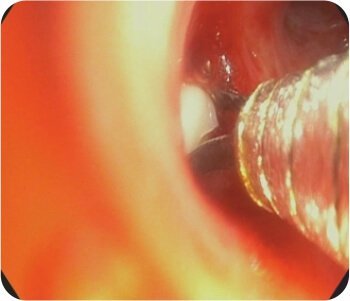

CT chest with thoracic angiogram revealed bilateral cavitary lesion with hypertrophied collateral arteries predominantly supplying the right upper lobe cavity. FOB done showed active bleeding from right upper lobe bronchus.

Watanabe sphigot occlusion of anterior subsegment of right upper lobe + glue instillation of right apical and posterior sub segment followed by bronchial artery embolization was done.

Placement of sphigot in right upper bronchus

Placement of sphigot in right upper lobe bronchus

Glue instillation in right upper lobe bronchus